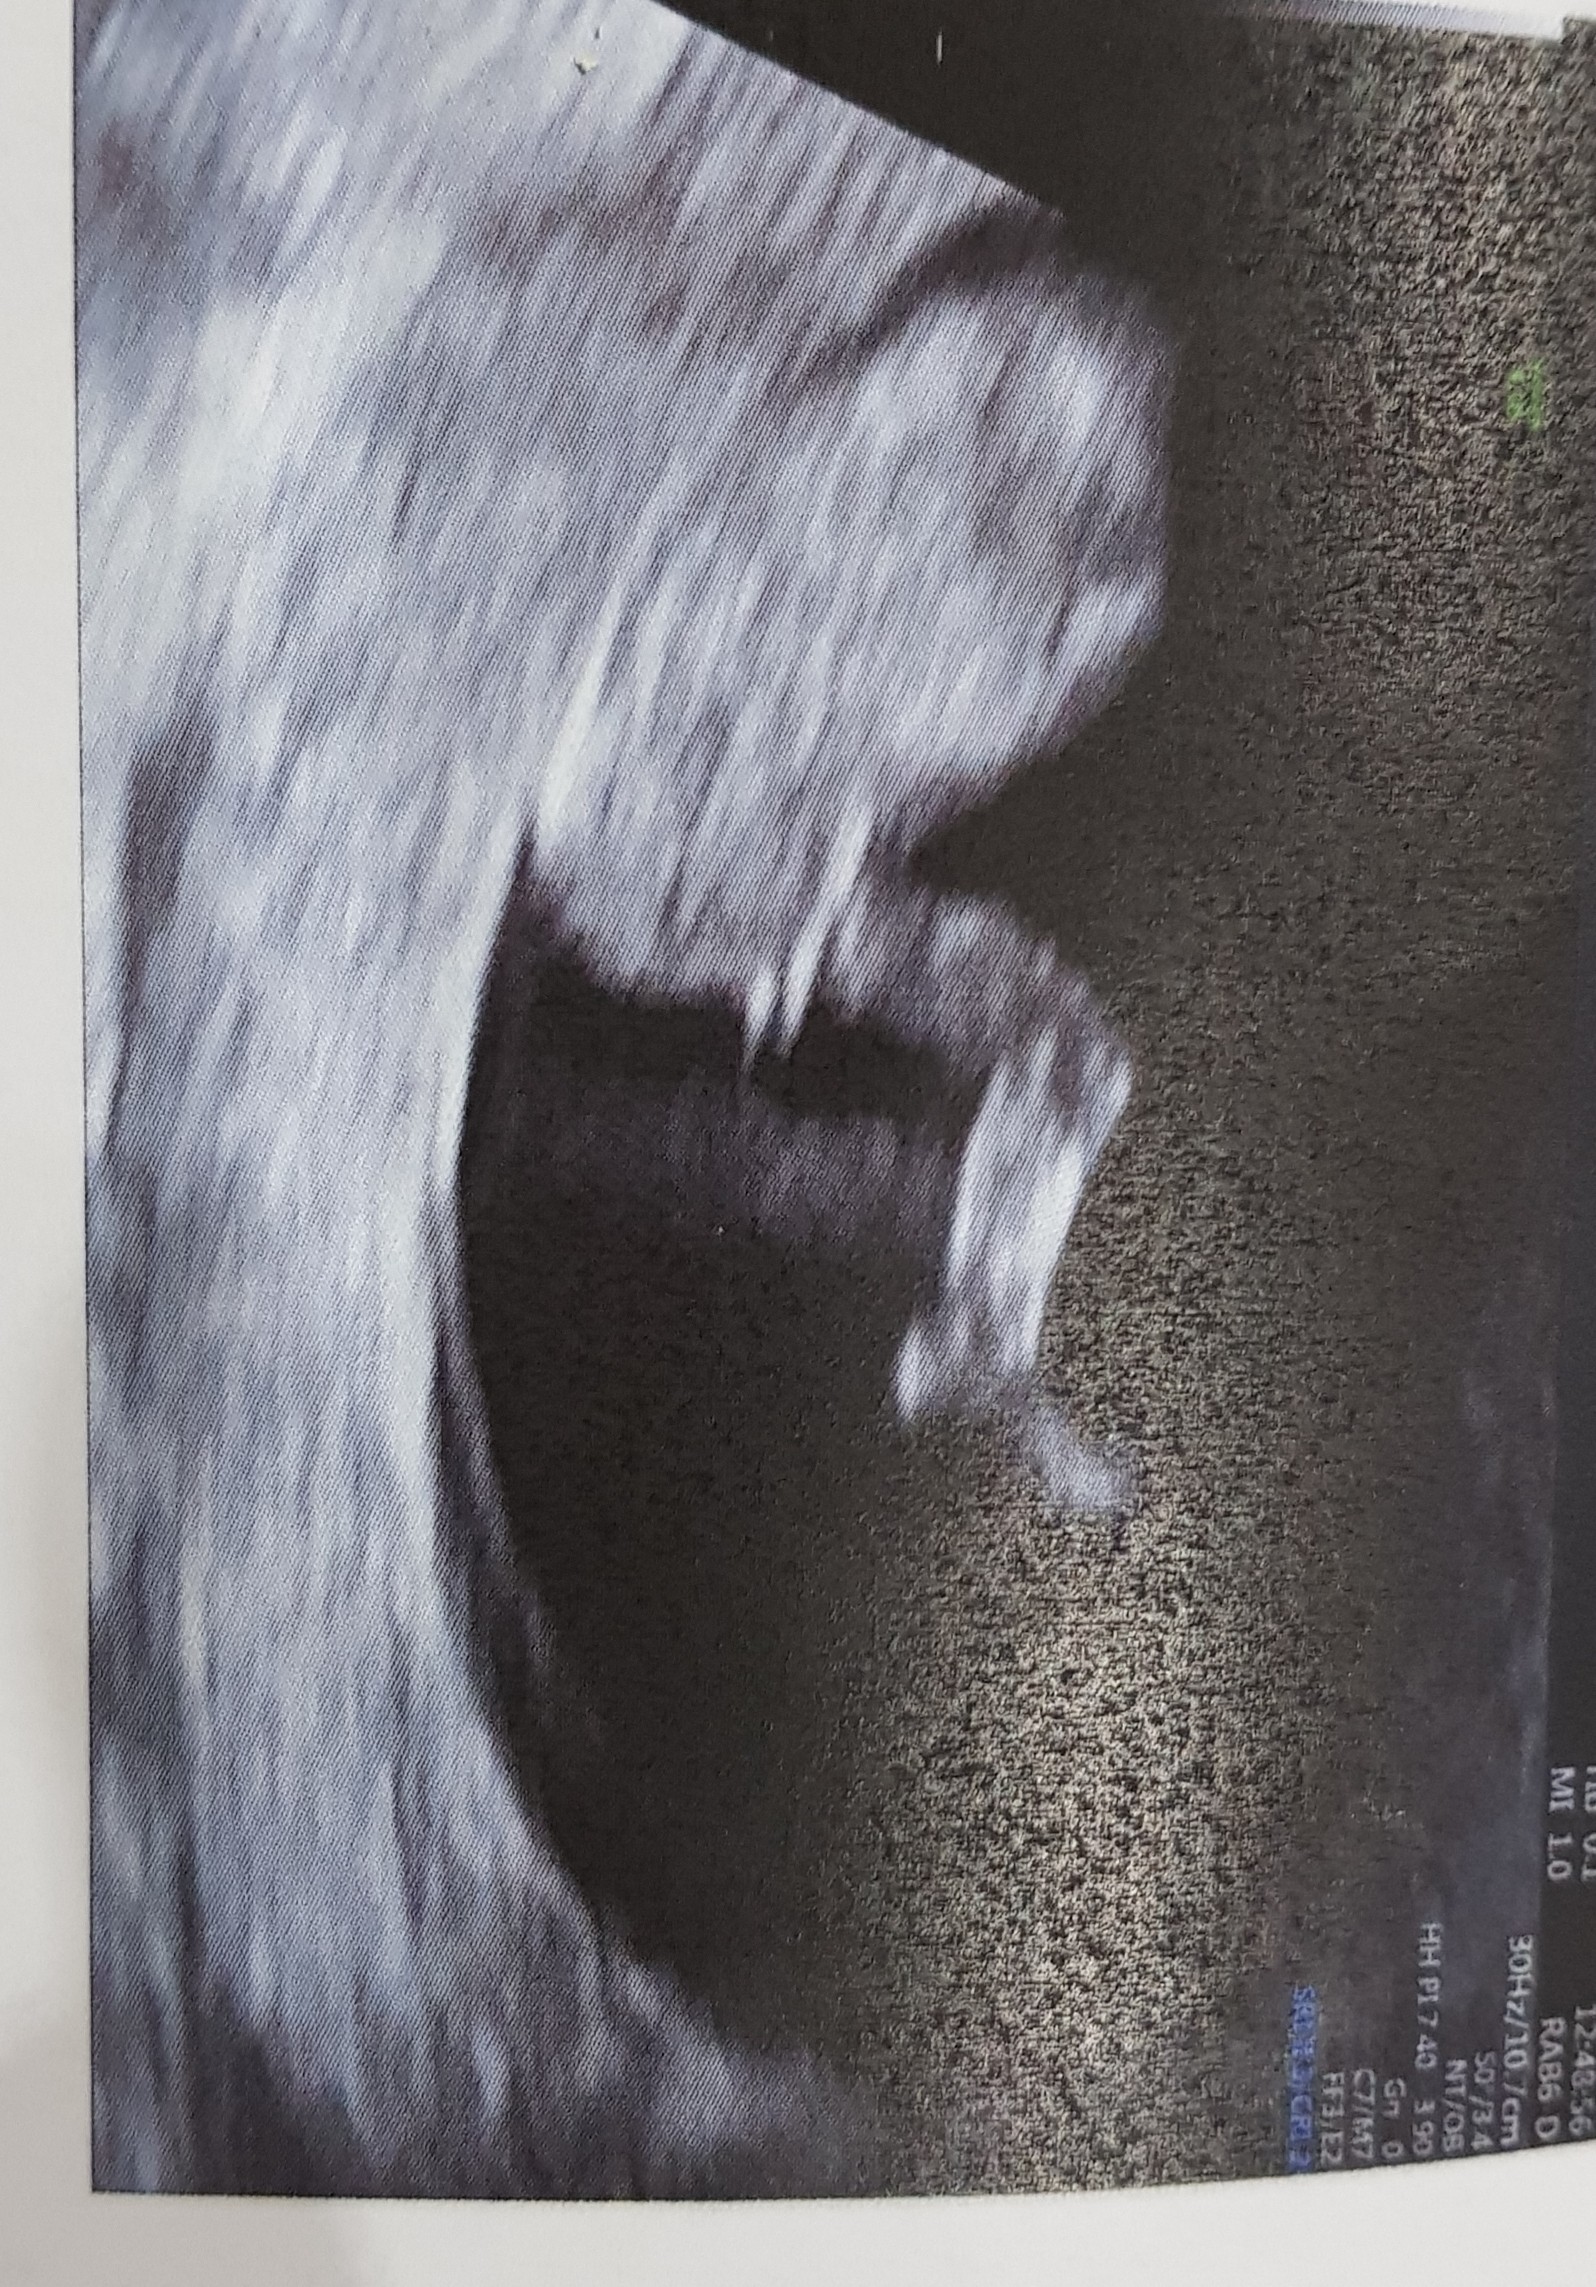

Witam, również mam termin na sierpień. Wrzucam zdjęcie z badań prenatalnych. I moje pytanie czy na zdjęciu widać wyrostek płciowy, I czy wróży to chłopca czy dziewczynkę?

• 20200216_162017.jpg

20200216_162017.jpg

1,3 MB · Wyświetleń: 139